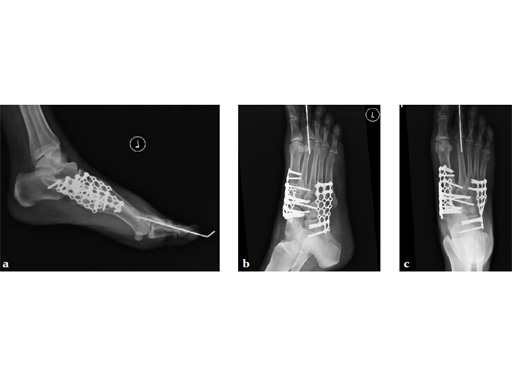

Case 7: VA -locking X-plate

A 49-year-old woman had extreme pain in the talonavicular joint.

Case provided by Andrew Sands, New York, New York, USA

As isolated fusion of the talonavicular joint is often hard to achieve, a 4.0 mm lag screw a plus X-plate was used (see Fig. 2a-c).

Fusion of the talonavicular joint while saving the rest of the hindfoot complex motion was achieved (see Fig. 4a-c).